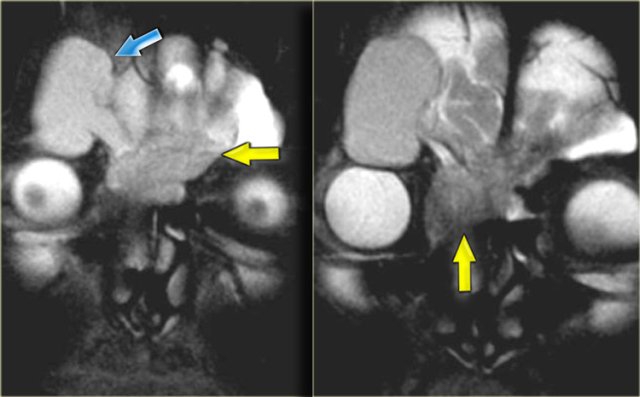

Brain abscess Brain abscess

Brain abscess

On the left images of a patient was initially diagnosed with a glioblastoma multiforme. There are abnormalities in both frontal lobes.

Notice however the abnormal tissue in the frontal sinus (yellow arrow), subperiosteal abscess (red arrow) and the fluid-fluid level (green arrow) in the large intracranial lesion which has ring enhancement.

All abnormalities are continuous meaning there is frontal bony destruction.

The restricted diffusion also supports the diagnosis of brain abscess.

This is a subperiosteal abscess and osteomyelitis of the frontal bone, usually with a soft tender swelling of the forehead.

This is also called Pott's puffy tumor after Sir Pott, an English surgeon who first described this entity.